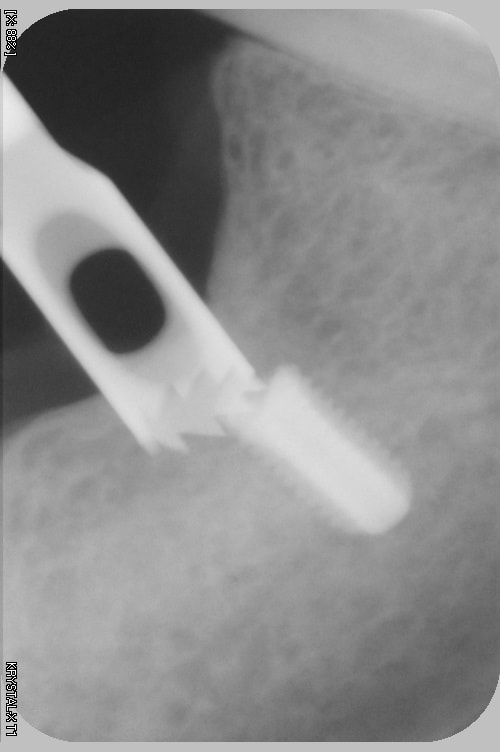

l'erreur vient dans ce cas pas du guide mais de mon inexpérience, le maillon faible ( de RENOUARD) c'est moi.

et là mauvaise nouvelle, j'ai voulu sortir l'implant , mais l'implant s'en va pour trois mois. va falloir sortrir la fraise à os, l'insert diamanté, et les loupes

à mon avis tu augmenter fortement tes problèmes si tu attends 3 mois, l'os peut se reformer et tu ne trouveras plus ton implant.... si tu stress trop avec le patient, fais toi assister par un confrère le patient ne t'en voudra pas.

2 solutions: soit retirer l'implant soit faire une empreinte et faire faire un pilier long (titane) lisse qui va transformer ton implant en transosseux/transmuqueux... si tu n'as pas de ciment pour la jonction c'est tout à fait jouable.

soit tu t'amuse à l'enlever (le plus simple est de trouver un outil long et de dévisser, ou bien: le trépan....

perso j'irai le chercher de suite...

pour moi la solution peut etre l'utilisation d'un tourne à gauche à la clé à main.

si l'espace interdentaire le permet.

comme les autres, je te conseil d'agir au plus vite.

si nécessaire meuler l'épaulement pour insérer à nouveau le porte implant ainsi tu as les 2 possibilités ou remonter en rotation ou en traction puisque la vis le maintiendra à l'implant.

oui finalement, lambeau , j ai enlevé de l os à la fraise, puis à la fin avec un insert à boule diamantée, pour finir sans abîmer la tête de vis ( conseil que j avais lu sur eugenol). Puis j ai mis une grosse vis de cicat.

Trois semaines plus tard j ai fait mon empreinte puis mis la couronne scellée (,cvimar) sur pilier vissé